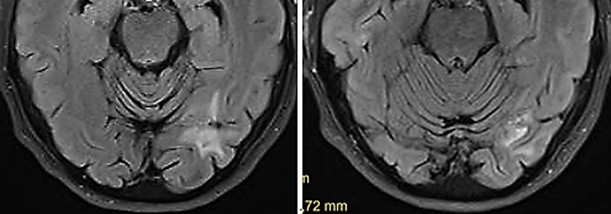

August 2025

After transcranial TMI treatment as described, the patient was becoming increasingly alert and showed improvement in all neurological investigations. With the support of the physiotherapist, he could now walk short distances and climb one flight of stairs, use the toilet independently, his spatial awareness was steadily improving, he could eat independently, and had complete recollection of all events up to the onset of somnolence. He had no memory of the eight weeks of somnolent state. A follow-up MRI of the skull shows the previously identified hemorrhagic area surrounded by a glial capsule and a perifocal edema, but no further progression of the metastasis. The TMI reated thalamic metastasis had shrunk considerably though it is unsure if there remained still vital tumorous tissue (Fig. 5). It must be underlined that the surrounding brain tissue was not impaired or damaged by TMI treatment, so that the patient clinically improved, unexpectedly gained again full neurological control, could leave the hospital and return home.

Fig. 5

Fig. 5: Metastasis in the right thalamus before transcranial TMI treatment with pronounced perifocal edema (left) and five months after TMI treatment; notably the brain tissue is not impaired by the transcranial TMI treatment (right).